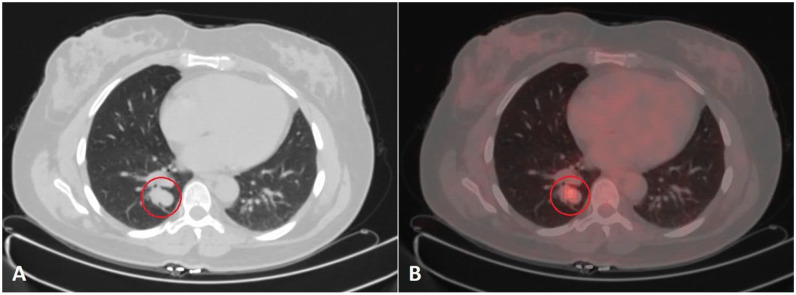

肺神经内分泌肿瘤包括神经内分泌癌和神经内分泌肿瘤(NETs)。net也被称为类癌(CaTs),分为典型类癌和非典型类癌(AC)。肺部cat常转移到不同部位,包括局部淋巴结、肺、肝和骨;然而,转移到大脑是相对罕见的。早期出现脑转移的患者更是罕见。我们报告一例50岁的女性患者,她最初表现为神经系统症状和磁共振成像结果提示多发性硬化症。尽管最初的治疗是多发性硬化症,但进一步的评估发现了一个罕见的支气管肺AC肿瘤转移到脑部的病例。本病例强调了在出现非典型神经症状的患者中考虑转移性疾病的重要性,特别是当初始治疗未能产生预期结果时。我们的文献回顾显示了7例最初表现为脑转移的cat,我们的患者是所有已发表病例中最年轻的。

Neuroendocrine neoplasms of the lung include neuroendocrine carcinomas and neuroendocrine tumors (NETs). NETs are also known as carcinoid tumors (CaTs), which are categorized as typical carcinoid and atypical carcinoid (AC). Pulmonary CaTs often metastasize to various sites, including regional lymph nodes, lungs, liver, and bone; however, metastasis to the brain is relatively rare. It is even rarer for patients with CaTs to present with signs of brain metastasis initially. We report the case of a 50-year-old female patient who initially presented with neurological symptoms and magnetic resonance imaging findings suggestive of multiple sclerosis. Despite initial treatment for multiple sclerosis, further evaluation uncovered a rare case of bronchopulmonary AC tumor metastasis to the brain. This case highlights the importance of considering metastatic disease in patients presenting with atypical neurological symptoms, especially when initial management fails to yield expected outcomes. Our literature review revealed 7 cases of CaTs initially presenting with brain metastases, with our patient being the youngest among all published cases.